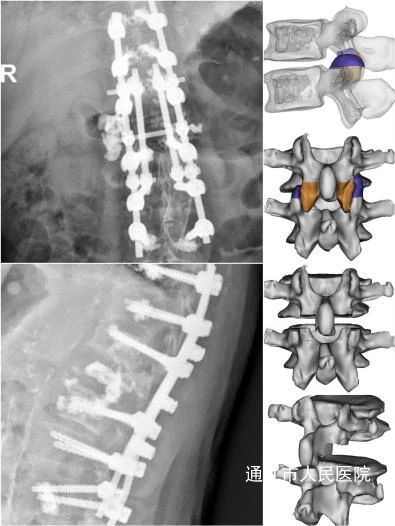

近日,我院脊柱外科应用Ponte截骨联合卫星棒技术成功为一位脊柱结核后凸畸形患者实施重建手术,标志着我院在界内脊柱矫形手术领域再获突破。

患者杨某某,74岁,女性,因胸腰背部疼痛10月余入住我院,该患者曾辗转多家医院,检查提示脊柱结核(T12-L2),为求进一步诊治遂前往我院就诊。针对患者恶病质体质病情特点,术前团队内部积极讨论手术方式。结合多学科会诊评估结果,与患者及家属充分沟通并征得同意后,房芳主任医师、胡宝阳主治医师在麻醉科医护人员的通力协作下,成功为患者实施胸椎后路切开椎板减压、Ponte截骨、骨水泥椎弓根钉内固定术(T10-L4),手术过程顺利,术后患者恢复良好,得到患者及家属一致好评。

脊柱截骨术因其截骨矫形操作手法复杂,一直以来被称作脊柱外科领域最具挑战的手术难题。面临极高神经血管损伤风险,若稍有不慎便会造成灾难性损伤,因此对手术操作的技术要求极高。卫星棒技术既满足了坚强固定需要又起到分散应力作用,术后矫形效果满意。本次手术的成功开展,将进一步引领我院脊柱外科深入研究探索该项技术的广袤前景。积极总结手术经验,不断完善操作流程,全力提高医疗服务水平,争取为更多患者提供更加安全、优质、高效的医疗服务,以推动我院及地区领域内脊柱外科医疗水平再上新台阶。